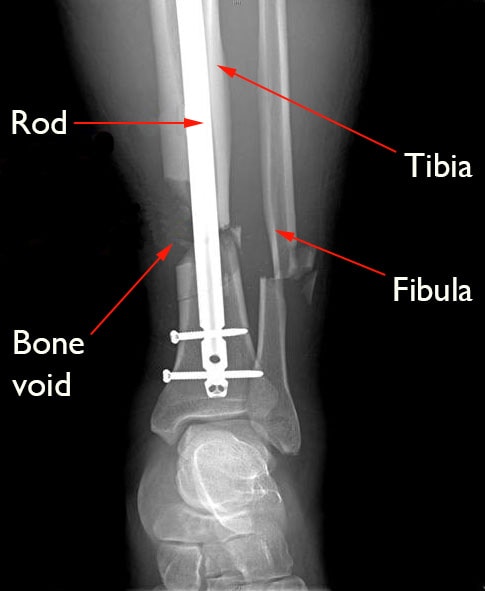

internal fixation of broken tibia

This X-ray shows a broken shinbone (tibia) with a large bone gap, or void. A metal rod has been placed down the marrow cavity of the bone to help hold it together.